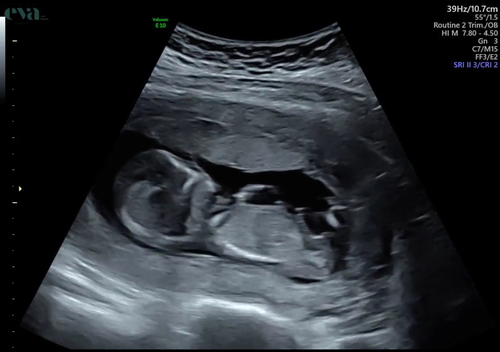

14 weken, ik denk een jongen?

Ik ook 🥹

Iemand een idee?💙💕

meisje